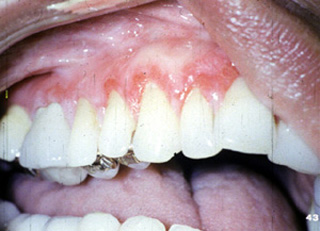

| Esta mujer 45

años de edad presenta úlceras

dolorosas de la encía alrededor de los dientes maxilares. El examen clínico

reveló la encía eritematosa con áreas

de ulceración. La higiene oral del paciente era buena y no había

evidencia radiográfica de enfermedad periodontal. No hay vesículas y ampollas; la piel no estaba involucrada. Esta condición era de un año

duración. No parecía cambiar en severidad durante ese tiempo.